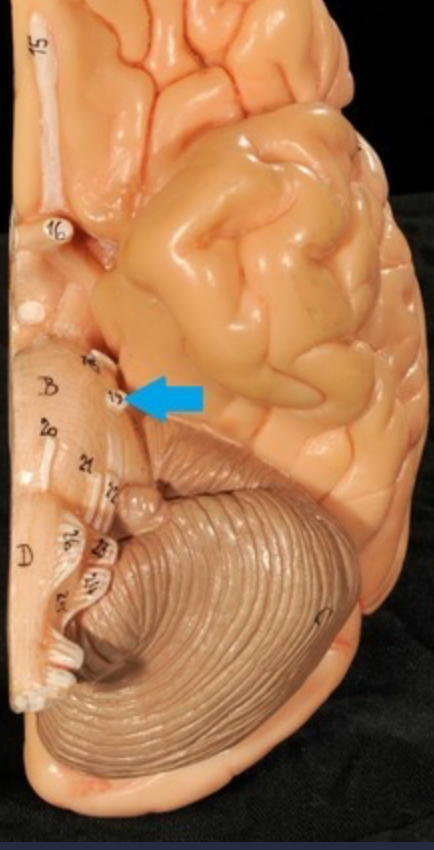

Brain stem

Pons

Medulla oblongata

I. Olfactory

II. Optic

III. Oculomotor

IV. Trochlear

V. Trigeminal

VI. Abducens

VII. Facial

VIII. Vestibulocochlear

IX. Glossopharyngeal

X. Vagus

XI. Accessory

XII. Hypoglossal